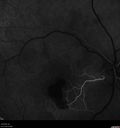

Perifoveal Microaneurysm - Not Diabetic (also reticular pseudodrusen)356 views87 year old female with fluctuating macular edema in the right eye from a perifoveal MA. (no treatment). VA 20/40 OUApr 02, 2020